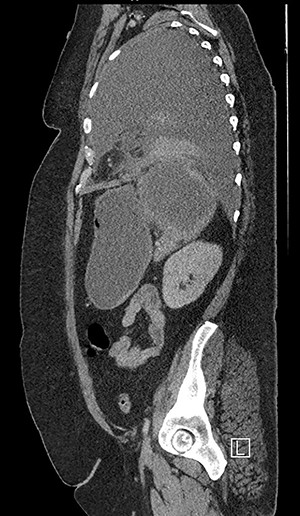

Forty-four-year-old clinically obese woman whose only past medical history was mild asthma with no use of systemic steroids. Initially presented with parapneumocic effusion following a recent bout of pneumonia which was not amenable to aspiration. Prior to this, the patient had experienced vague abdominal symptoms 1 month prior to the onset of the pneumonia. She was treated with oral amoxicillin. Twenty-five days later, she presented again in the Accident & Emergency Department with left-sided chest pain, left flank pain associated with fever and worsening dyspnea. Computed tomography (CT) scan (Fig. 1) showed a significant left-sided effusion with a complete collapse of the left lung and mild mediastinal shift towards the right. A 12.5 cm collection in the upper pole of the spleen was noted which appeared to extend through the diaphragm (Fig. 2). She was started on the sepsis pathway as per hospital protocol. A seldinger chest drain was inserted which immediately drained 1500 ml of pus. She underwent a thoracoscopic washout, debridement and decortication. The chest drains were removed 9 days post-operatively. She was transferred to General surgeons where a percutaneous drain (pigtail catheter) was inserted under ultrasound guidance. Three hundred and five milliliters in a total of pus was drained from the splenic abscess. Staphylococcus aureus was isolated from both the pleural and splenic collection. Blood cultures and transthoracic echocardiogram were unrevealing. A blood bourne virus screen (Hepatitis B, Hepatitis C, HIV) was negative as well. A repeat ultrasound scan showed complete resolution of the splenic abscess with normal splenic architecture.

CT chest, abdomen and pelvis coronal view: left-sided empyema and splenic abscess.